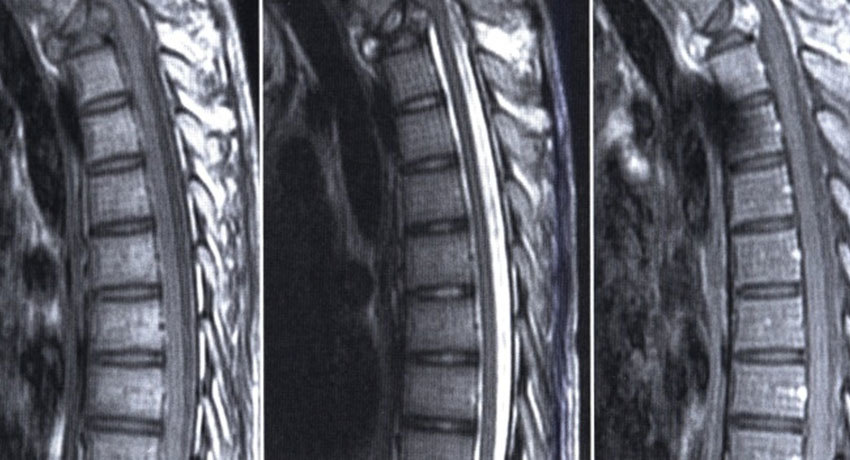

До 90% злокачественных новообразований, выявленных в позвоночном столбе, являются метастазами злокачественных опухолей, расположенных в других органах. Чаще всего в позвоночник метастазирует рак молочной железы, легкого, простаты, почек, желудочно-кишечного тракта, щитовидной железы.

В зависимости от конкретной клинической ситуации, схема лечения пациента с метастазами в позвоночном столбе может включать разные методики:

Лучевая терапия зачастую является основным методом лечения. Применяют как классическое внешнее облучение (cEBRT), так и стереотаксическую радиохирургию (SBS).

Вертебропластика и кифопластика — малоинвазивные вмешательства. Во время вертебропластики в разрушенный позвонок вводят иглу и заполняют его костным цементом. Во время кифопластики в позвонок сначала вводят специальный баллон и раздувают его изнутри, чтобы восстановить нормальную высоту позвонка, и после этого применяют цемент.

Открытые хирургические вмешательства предполагают стабилизацию позвоночного столба, резекцию опухолевых очагов, декомпрессию — устранение сдавления спинного мозга и нервных корешков. Обычно пациенты с метастатическим раком плохо переносят такие операции, у них высок риск осложнений. Открытые хирургические вмешательства целесообразны в случаях, когда ожидаемая продолжительность жизни пациента составляет более 3 месяцев, и имеются выраженные неврологические расстройства, сильное сдавление спинного мозга.